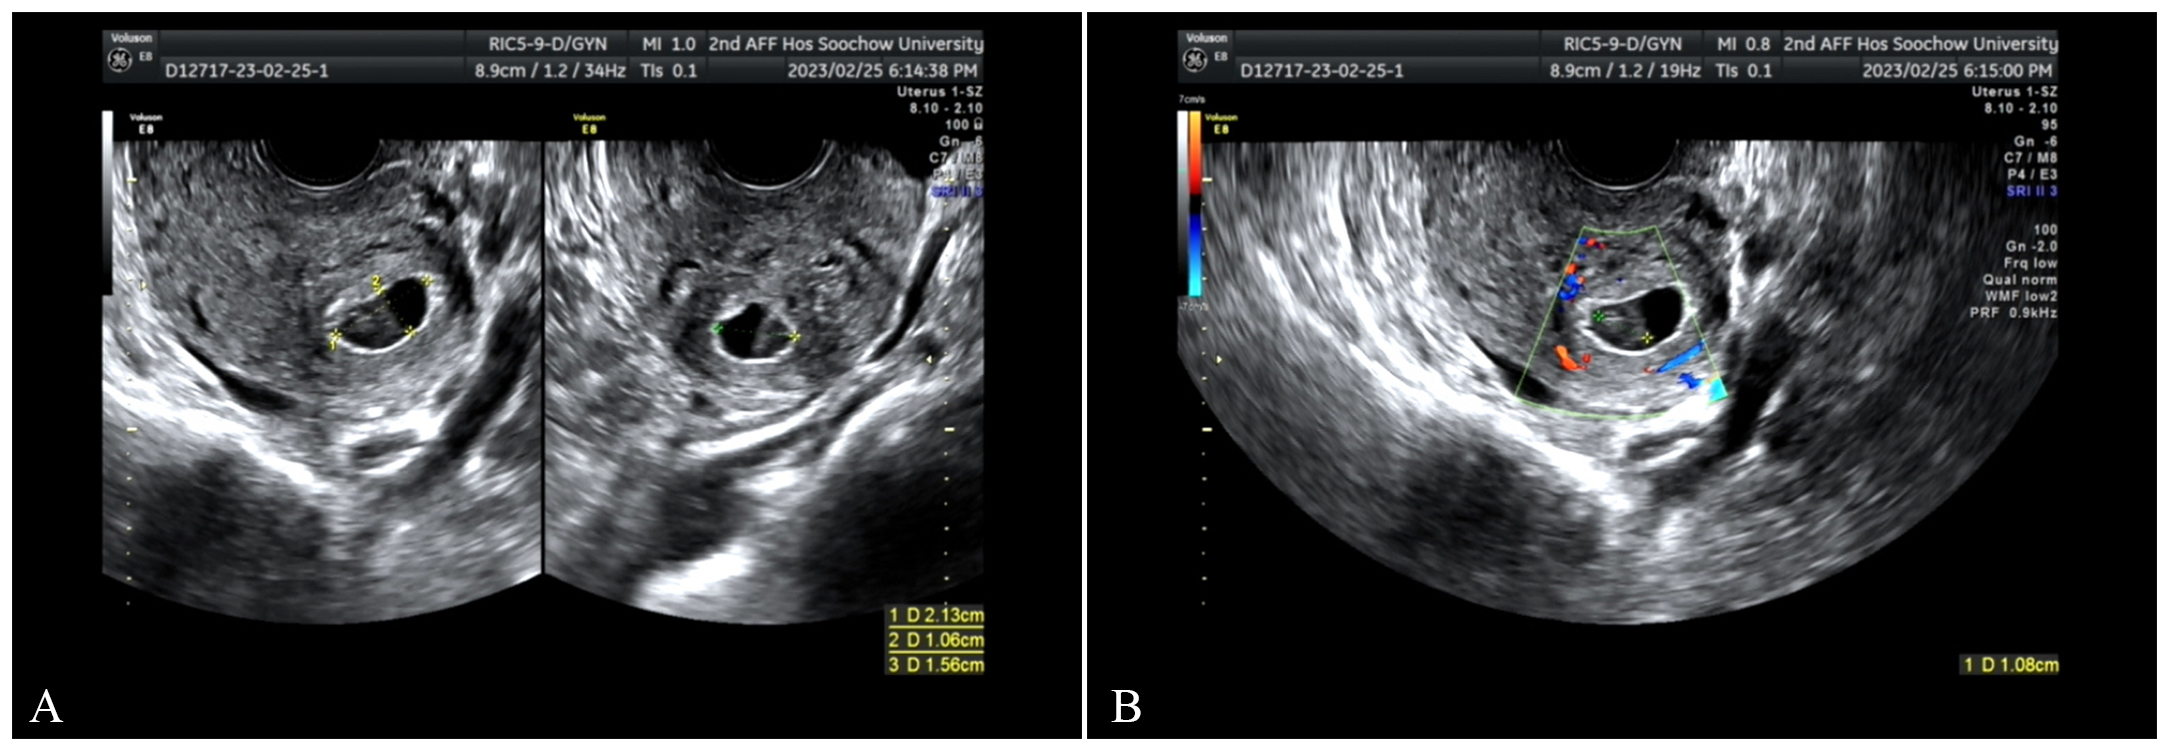

Fig. 2. On February 28, transvaginal three-dimensional ultrasound (TDU). (A) There was an echo of the gestational sac between the muscle walls. (B) Blood flow signals around it are increased.